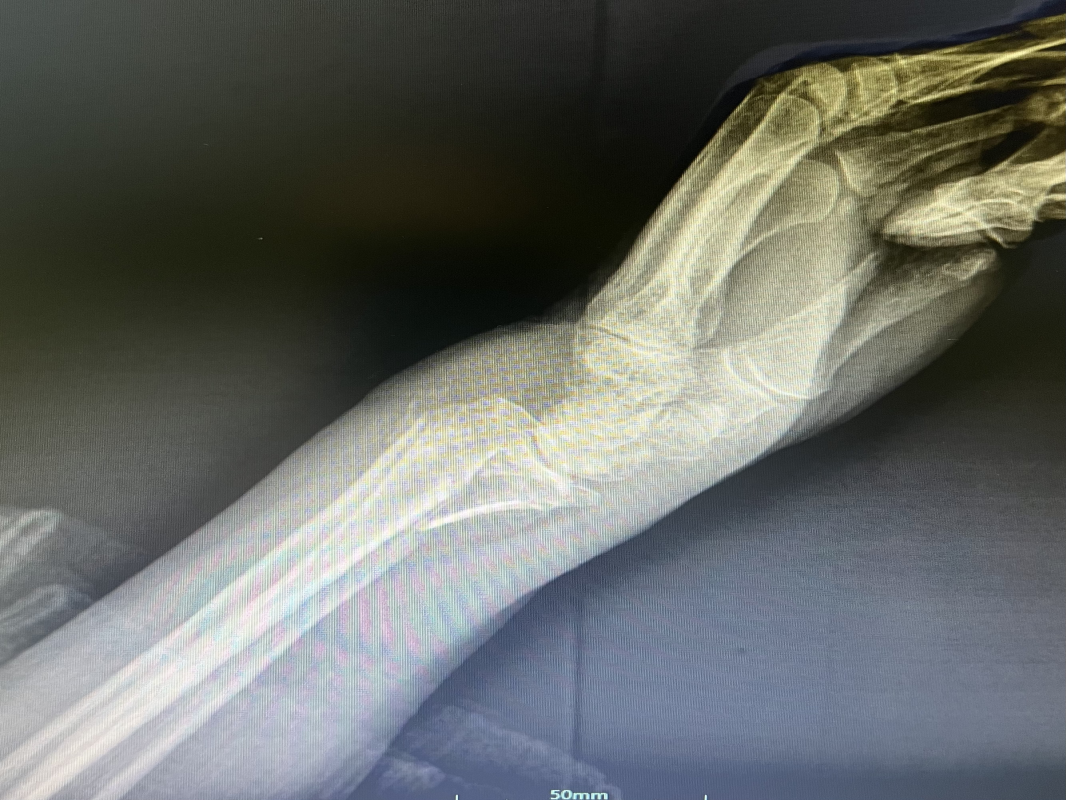

近日,我科收住一位高齡患者,孫某某,女,82歲,患者2小時(shí)前因摔傷致全身多處腫痛、伴活動(dòng)受限。入院后診斷:1.右股骨粗隆間粉碎性骨折;2.右尺橈骨遠(yuǎn)端粉碎性骨折;3.右鎖骨骨骨折;4.右肱骨大結(jié)節(jié)骨折;5.右恥骨下肢骨折;6.重度骨質(zhì)疏松。 鑒于患者屬高齡,損傷重,病情復(fù)雜,入科后科主任魏國(guó)華帶領(lǐng)關(guān)節(jié)骨科醫(yī)護(hù)團(tuán)隊(duì)積極完善相關(guān)檢查、科學(xué)制定治療方案,充分發(fā)揮中醫(yī)骨傷的治療優(yōu)勢(shì),保守與手術(shù)相結(jié)合,對(duì)右尺橈骨遠(yuǎn)端粉碎性骨折行手法復(fù)位石膏托外固定術(shù)。 排除手術(shù)禁忌后,在腰硬聯(lián)合麻醉下行右股骨粗隆間粉碎性骨折閉合復(fù)位PFNA內(nèi)固定術(shù),其余疾病行保守治療,術(shù)后經(jīng)活血化瘀、益氣養(yǎng)血等積極對(duì)癥治療,患者肢體功能恢復(fù)良好,已康復(fù)出院。 股骨粗隆間骨折是老年人常見(jiàn)損傷,俗稱人生最后一次骨折。老年人骨質(zhì)疏松,肢體不靈活,當(dāng)下肢突然扭轉(zhuǎn)、跌倒或使大粗隆直接觸地?fù)p傷,甚易造成骨折。由于粗隆部受到內(nèi)翻及向前成角的復(fù)合應(yīng)力,引起髖內(nèi)翻畸形和以小粗隆支點(diǎn)的嵌壓形成小粗隆蝶形骨折。亦可由髂腰肌突然收縮造成小粗隆撕脫骨折。粗隆部骨質(zhì)疏松脆,故骨折常為粉碎型。 就診地址:酒泉市中醫(yī)醫(yī)院關(guān)節(jié)骨科?? ?? 門診部:二樓205診室 住院部:綜合樓6樓住院部